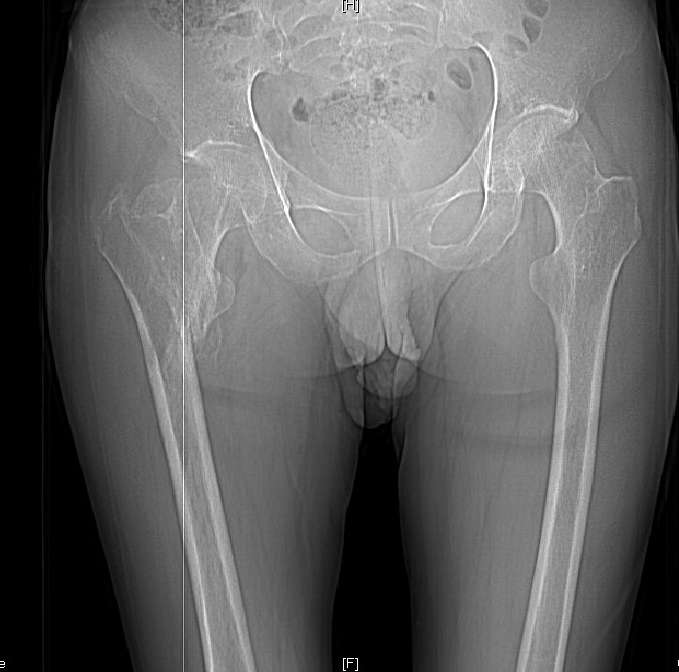

Доброго времени суток, уважаемые коллеги! Больному 45 лет. Лечили в сельской больнице на скелетном вытяжении 6 нед. по поводу межвертельного перелома бедренной кости с последующим наложением кокситной повязки еще на 2 мес.

С момента травмы прошло 5 месяцев, ходит с костылями без нагрузки, контрактуры в коленном и в тазобедренном суставах. Снимки во вложении. У нас мнения разделились. Показанием для открытого остеосинтеза мы считаем неустраненное ротационное смешение дистального фрагмента, которое может привести к нарушению биомеханики в тазобедренном суставе с последющими вытекающими последствиями. ЭОП на сегодняшний день недоступен нам, а остеосинтез угловыми пластинами, что можно попытаться, имеет определенный риск. Как быть? Начать разработку в суставах и активизировать больного, что не было сделано до этого, или всё-таки оперировать? Будем рады Вашим советам.

Никаких особенных проблем не видно, оперировать не видно, ради чего. Большого ротационного смещения нет, тазобедренный сустав - шаровидный, такие смещения прощает. Укорочение есть, но небольшое.

A что Вы думаете по поводу консолидации? Если имеется, почему до сих пор ходит с костылями? Если нет - о какой разработке суставов идет речь? Судя по рентгенограмме - не срослось. По КТ - ткань розового цвета между отломками такая же, как та, что покрывает головку. Тоже вроде не срослось. Мужику 45 лет. Конечно оперировать.

Доброй ночи, коллеги! И о чем спорим? Ротация не большая, укорочение не значительное,сустав относительно благополучен. Необходима дозированная нагрузка, разработка сустава - пусть человек живет и ходит. Если что-то пац-та будет не устраивать в последующем времени - задумайтесь о коррегирующей остеотомии с множеством методов фиксации без помощи ЭОПа.